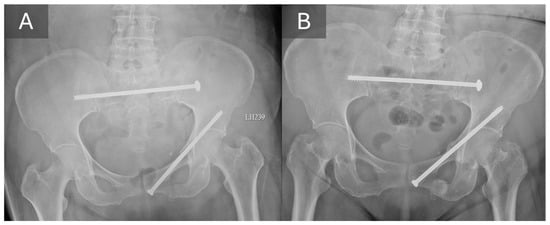

3.3. Radiographic Outcomes